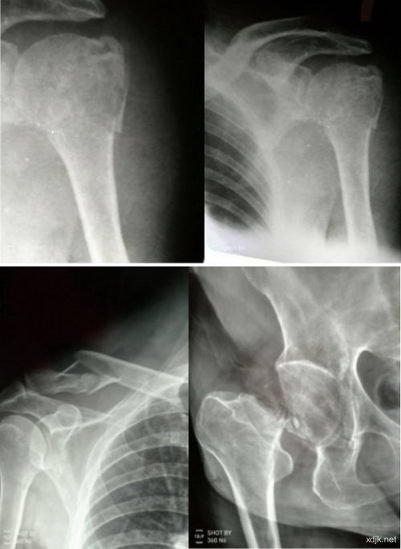

5、王秀梅,女,88岁,电话;137*****269,左第二根肋骨根部骨折,左肱骨近端骨折,2015年3月23日来诊,用药两周症状完全消失,活动正常,这是一例年龄最大,恢复最快的医案。